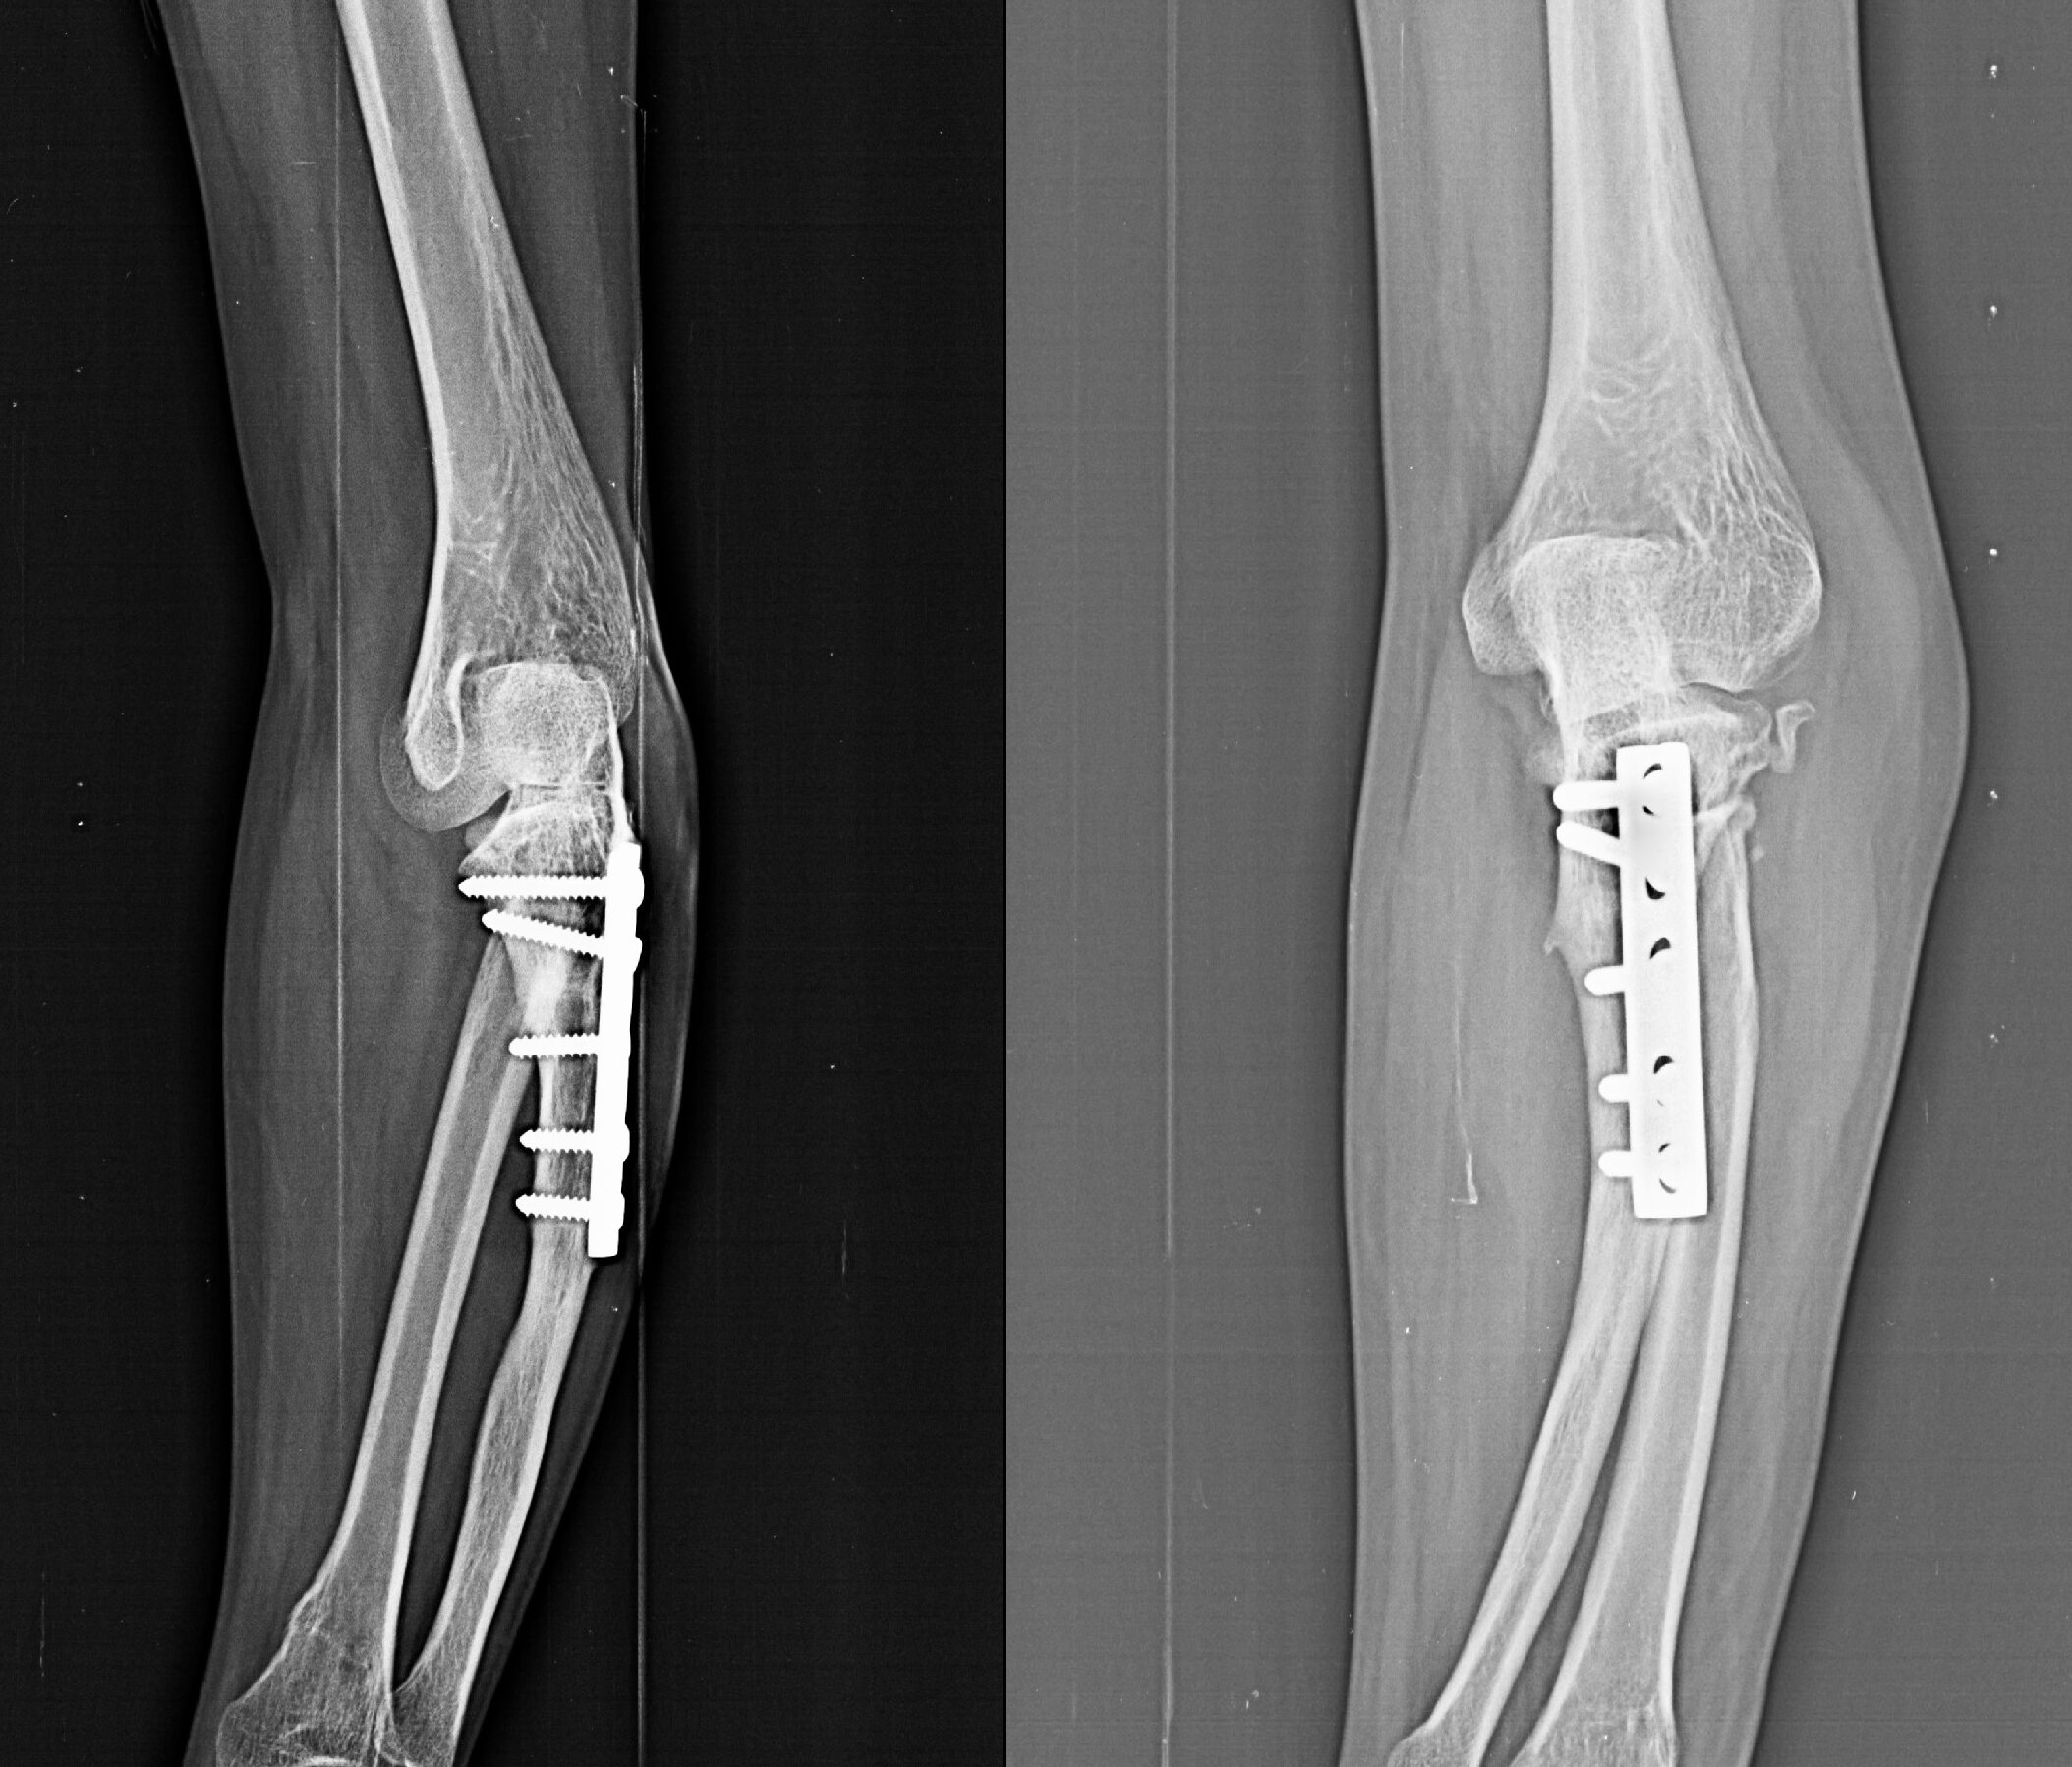

Post-traumatic Elbow Deformity